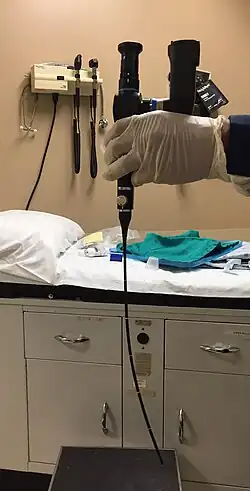

Initial diagnosis requires visualisation of the tumour either through the mouth or endoscopically through the nose using a rhinoscope, illustrated to the right, followed by biopsy.